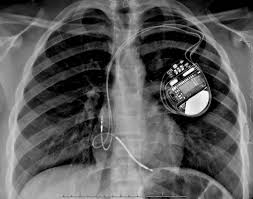

Sometimes, pacemaker and icd leads stop working properly due to damage or scar tissue accumulation. Pacemaker and icd troubleshooting, 2016. Like a pacemaker, an implantable cardioverter defibrillator, or icd, is a device placed under your skin. Implantable cardioverter defibrillators (icds) have a similar appearance to pacemakers. Implanting a pacemaker in your chest requires a surgical procedure. Temporary or permanent modification of the function (i.e., damage). Implantable cardiac conduction devices (also known as cardiac implantable electronic devices or cieds) are a very common medical device of the thorax cardiac pacemakers may be temporary or permanent, with the latter commonly known by the acronym ppm (permanent pacemaker). Pacemaker and icd manufacturers are arranged in alphabetical order with devices organized in numeric sequence.

Sometimes, pacemaker and icd leads stop working properly due to damage or scar tissue accumulation. An implantable cardioverter defibrillator (icd) looks similar to a pacemaker, though slightly larger. Which pacemaker/icd is that again. A pacemaker is a small device implanted in the chest. Pacemaker & icd are two different devices. Start studying pacemakers & icds. Movement and/or vibration of the pulse generator or leads. Die icd elektroden liegen regelrecht im rechten vorhof und im rechten ventrikel. Doctors also treat arrhythmias with implantable cardioverter defibrillators (icds). Icds are similar to pacemakers. Another type of pacemaker is called a biventricular pacemaker. Pacemaker and icd troubleshooting, 2016. Paces the heart muscles by providing an electrical.

Implanting a pacemaker in your chest requires a surgical procedure. Pacemaker and icd troubleshooting, 2016. How does a pacemaker work? It also contains a computer that tracks your national heart, lung, and blood institute: Another type of pacemaker is called a biventricular pacemaker. An implantable cardioverter defibrillator (icd) looks similar to a pacemaker, though slightly larger. Once the wires are in place, your doctor will make a small cut into the. Temporary or permanent modification of the function (i.e., damage). ©2021 daily search trends feedback. Pertinent factors relating to each manufacturer's devices are referenced according to: Devices that may interfere with icds and pacemakers. It works very much like a pacemaker. While pacemaker's job is to treat slow heart rate, icd's job is to treat very fast chaotic heart rhythm.